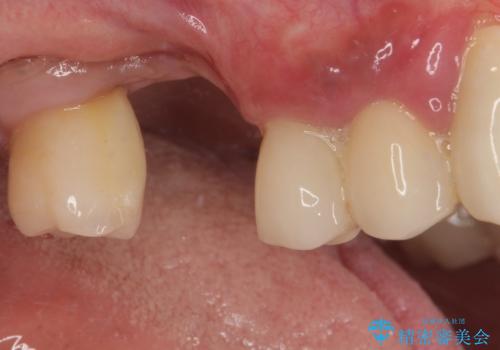

- インプラントが脱落してしまったとのことで来院された患者様です。

歯肉は綺麗に治癒しており、インプラント埋入に十分な骨があったため、速やかにインプラント埋入を行うこととしました。

インプラント埋入の状態が良ければ即日で仮歯を装着し、十分な生着が確認され次第、オールセラミッククラウンにて補綴治療を行うこととしました。